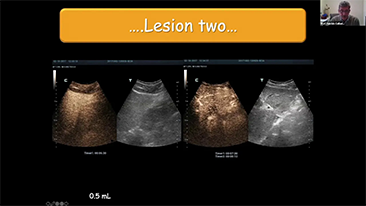

Per le lesioni focali epatiche, come l'emangioma o il tumore al fegato, l'imaging di contrasto a ultrasuoni svolge un ruolo importante. La tecnologia di imaging di contrasto Ultra-wideband non-linear UWN+ consente di ottenere una migliore penetrazione, un rapporto contrasto-tessuto pi├╣ elevato con un indice meccanico pi├╣ basso e un'osservazione del tempo di perfusione pi├╣ lunga.